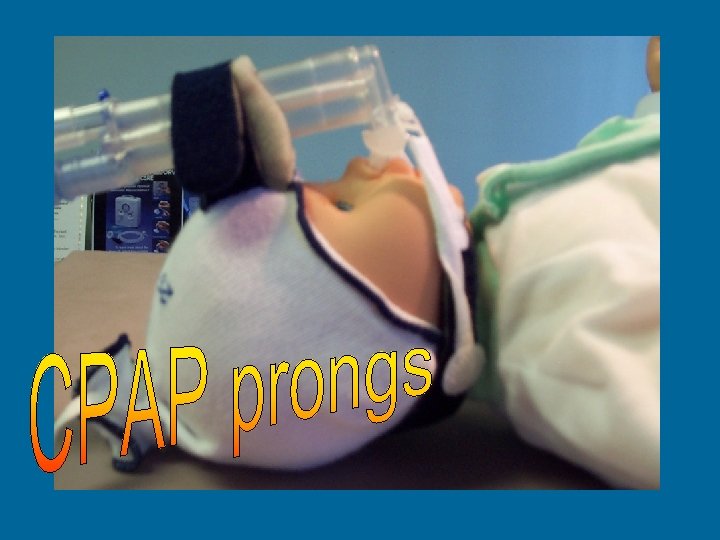

Duo. Derm • Nare protection from CPAP prongs • Nasal seal for CPAP prongs